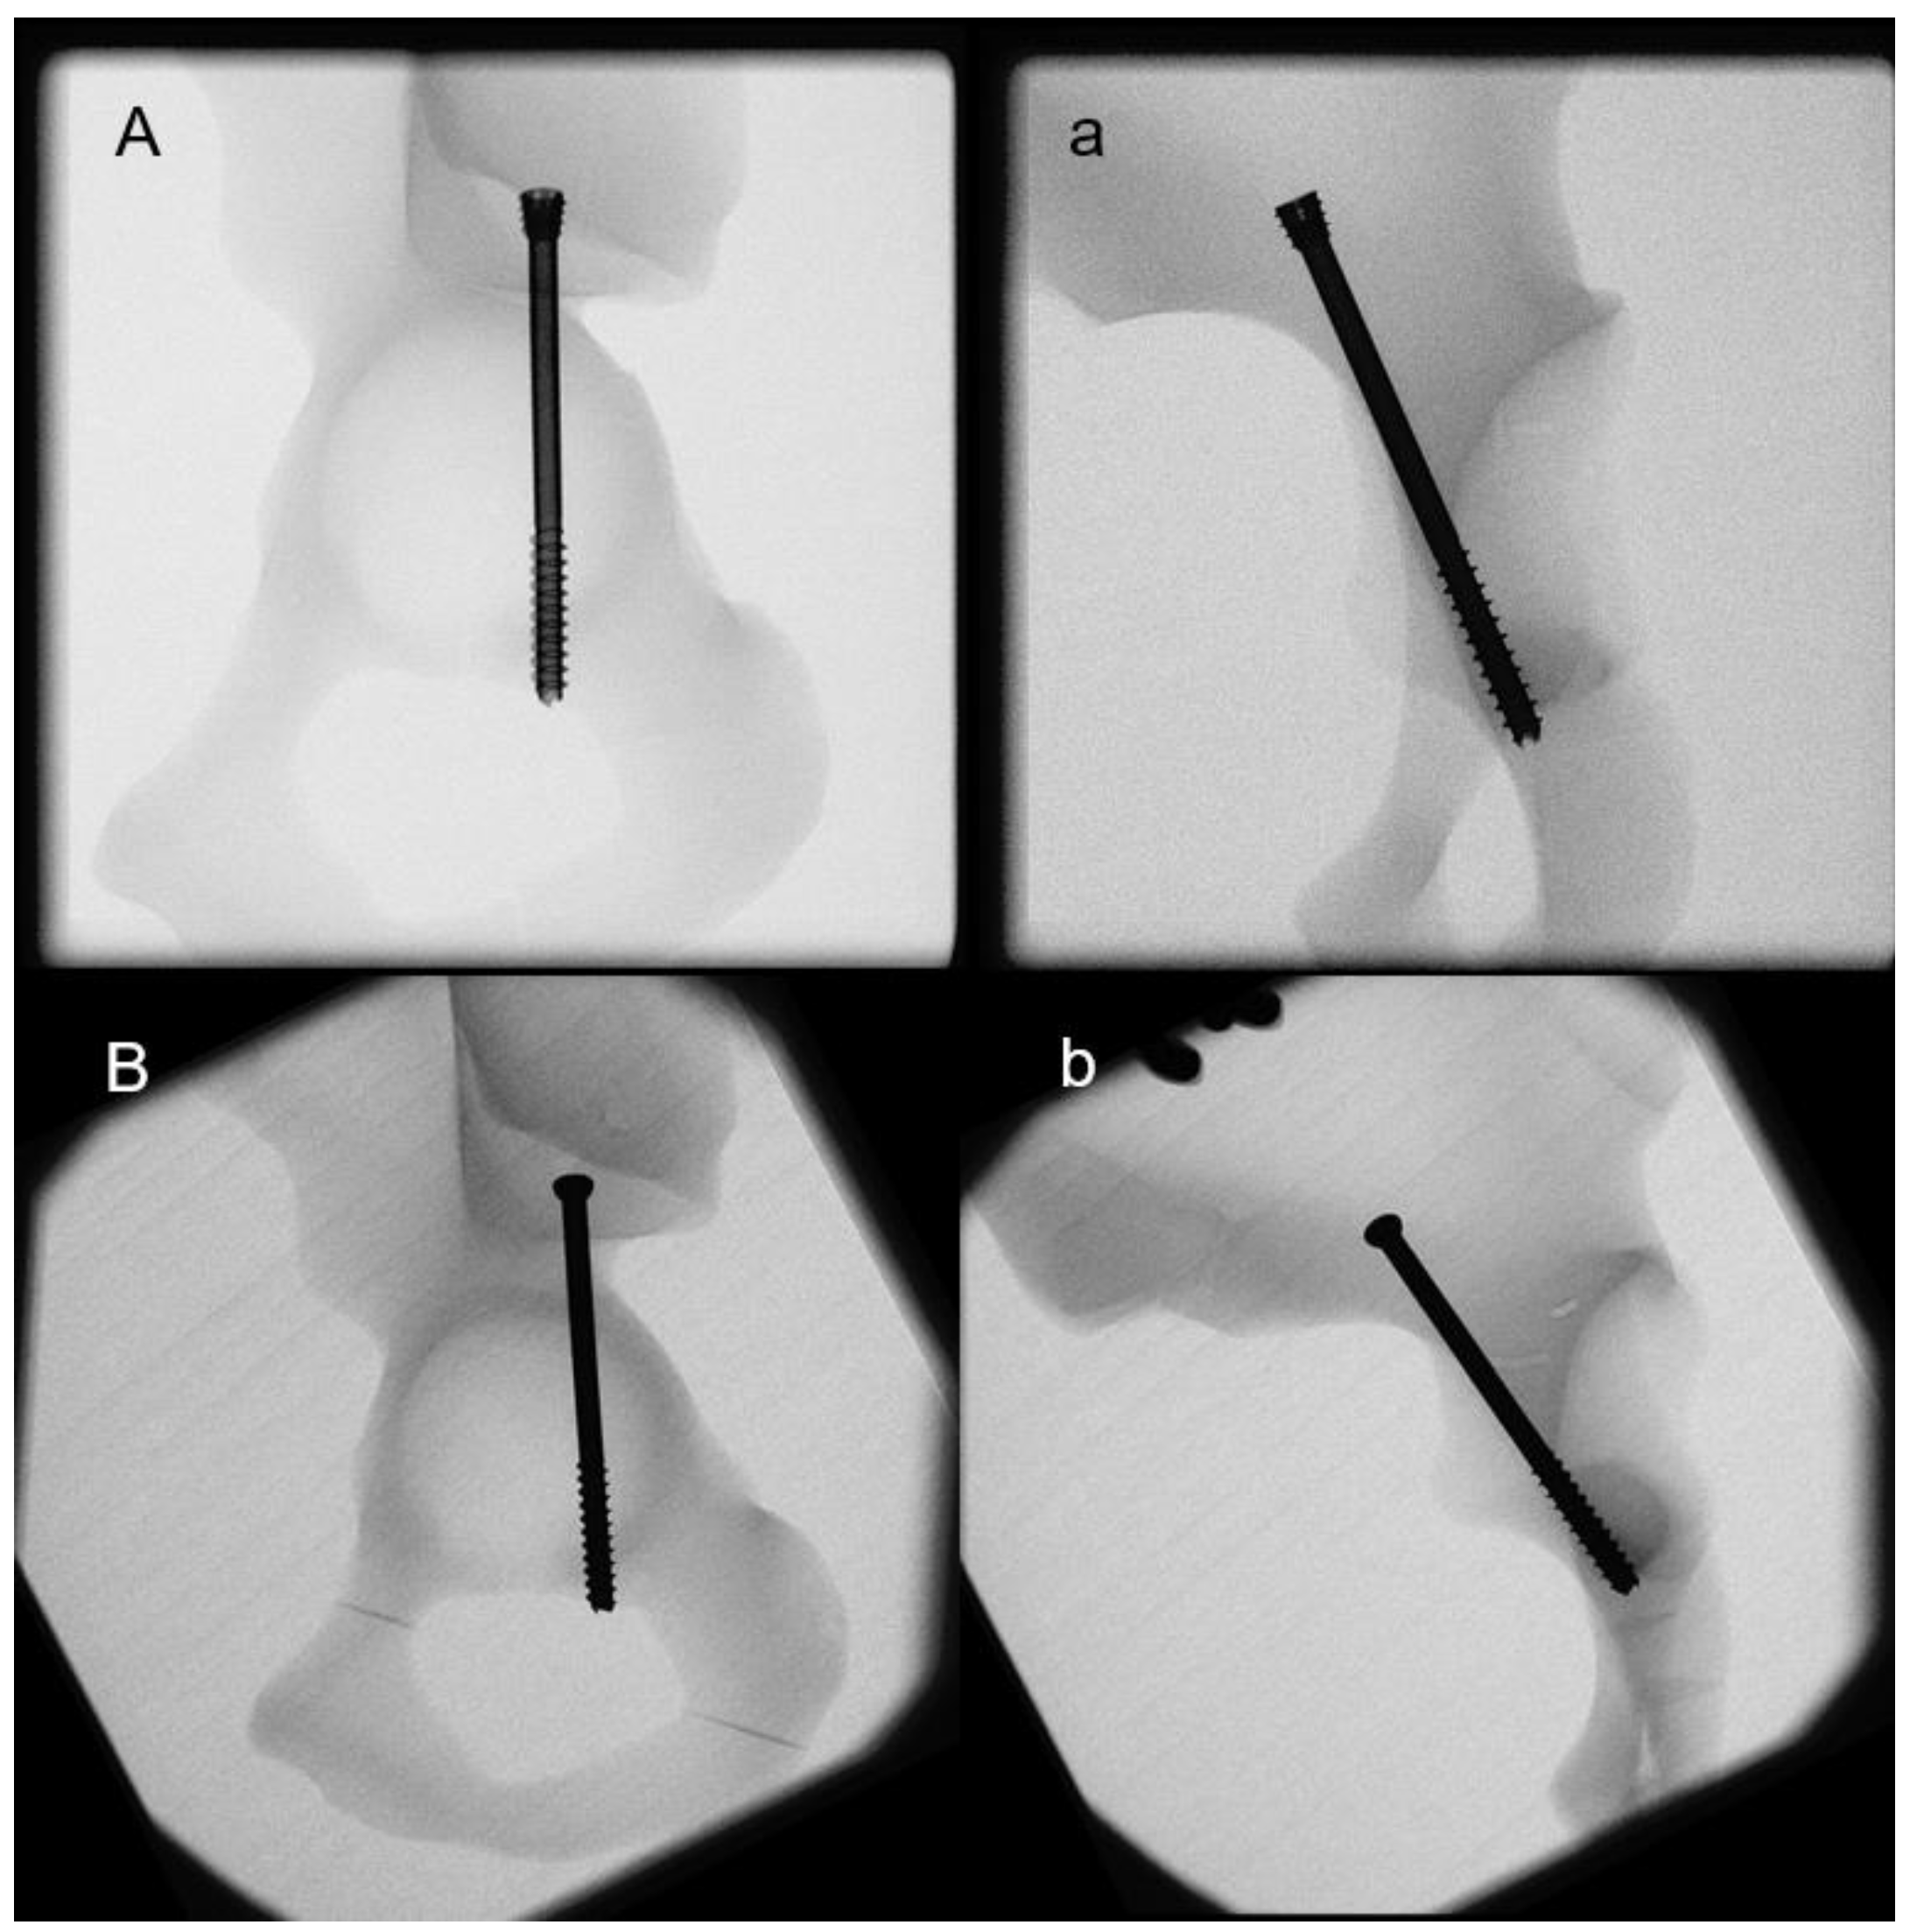

2. Materials and Methods

2.1. Biomechanical Testing